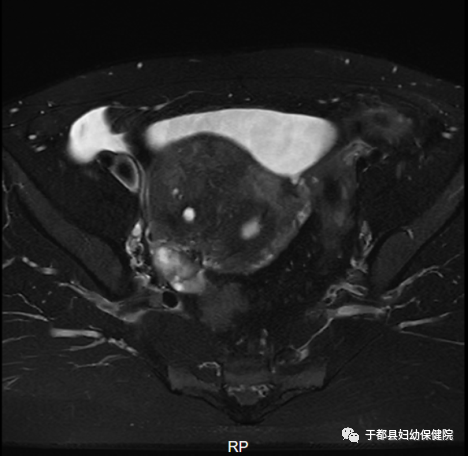

胎盘植入:不受患者体重及胎盘位置的影响,可以更好地观察胎盘、确定胎盘植入程度,有助于临床选择合适的治疗手段。